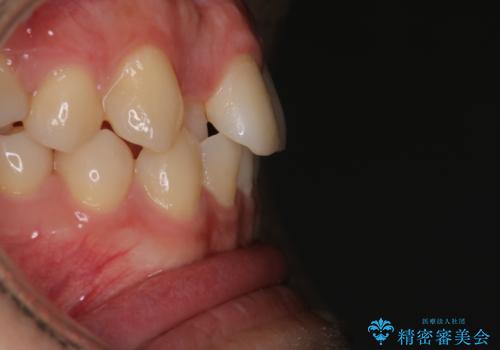

- 前歯のがたつきを主訴に来院されました。初診時、右上2番の口蓋側転位と右下7番の舌側傾斜が認められました。

インビザラインにてIPRと歯列弓拡大を行い、ゴム掛けで噛み合わせを改善する治療計画を立てました。

マウスピースの使用時間が短いため、シュミレーション通り進むか不安でしたが

治療期間1年で、主訴である前歯のがたつきを改善出来、

奥歯の噛み合わせも良くなりました。